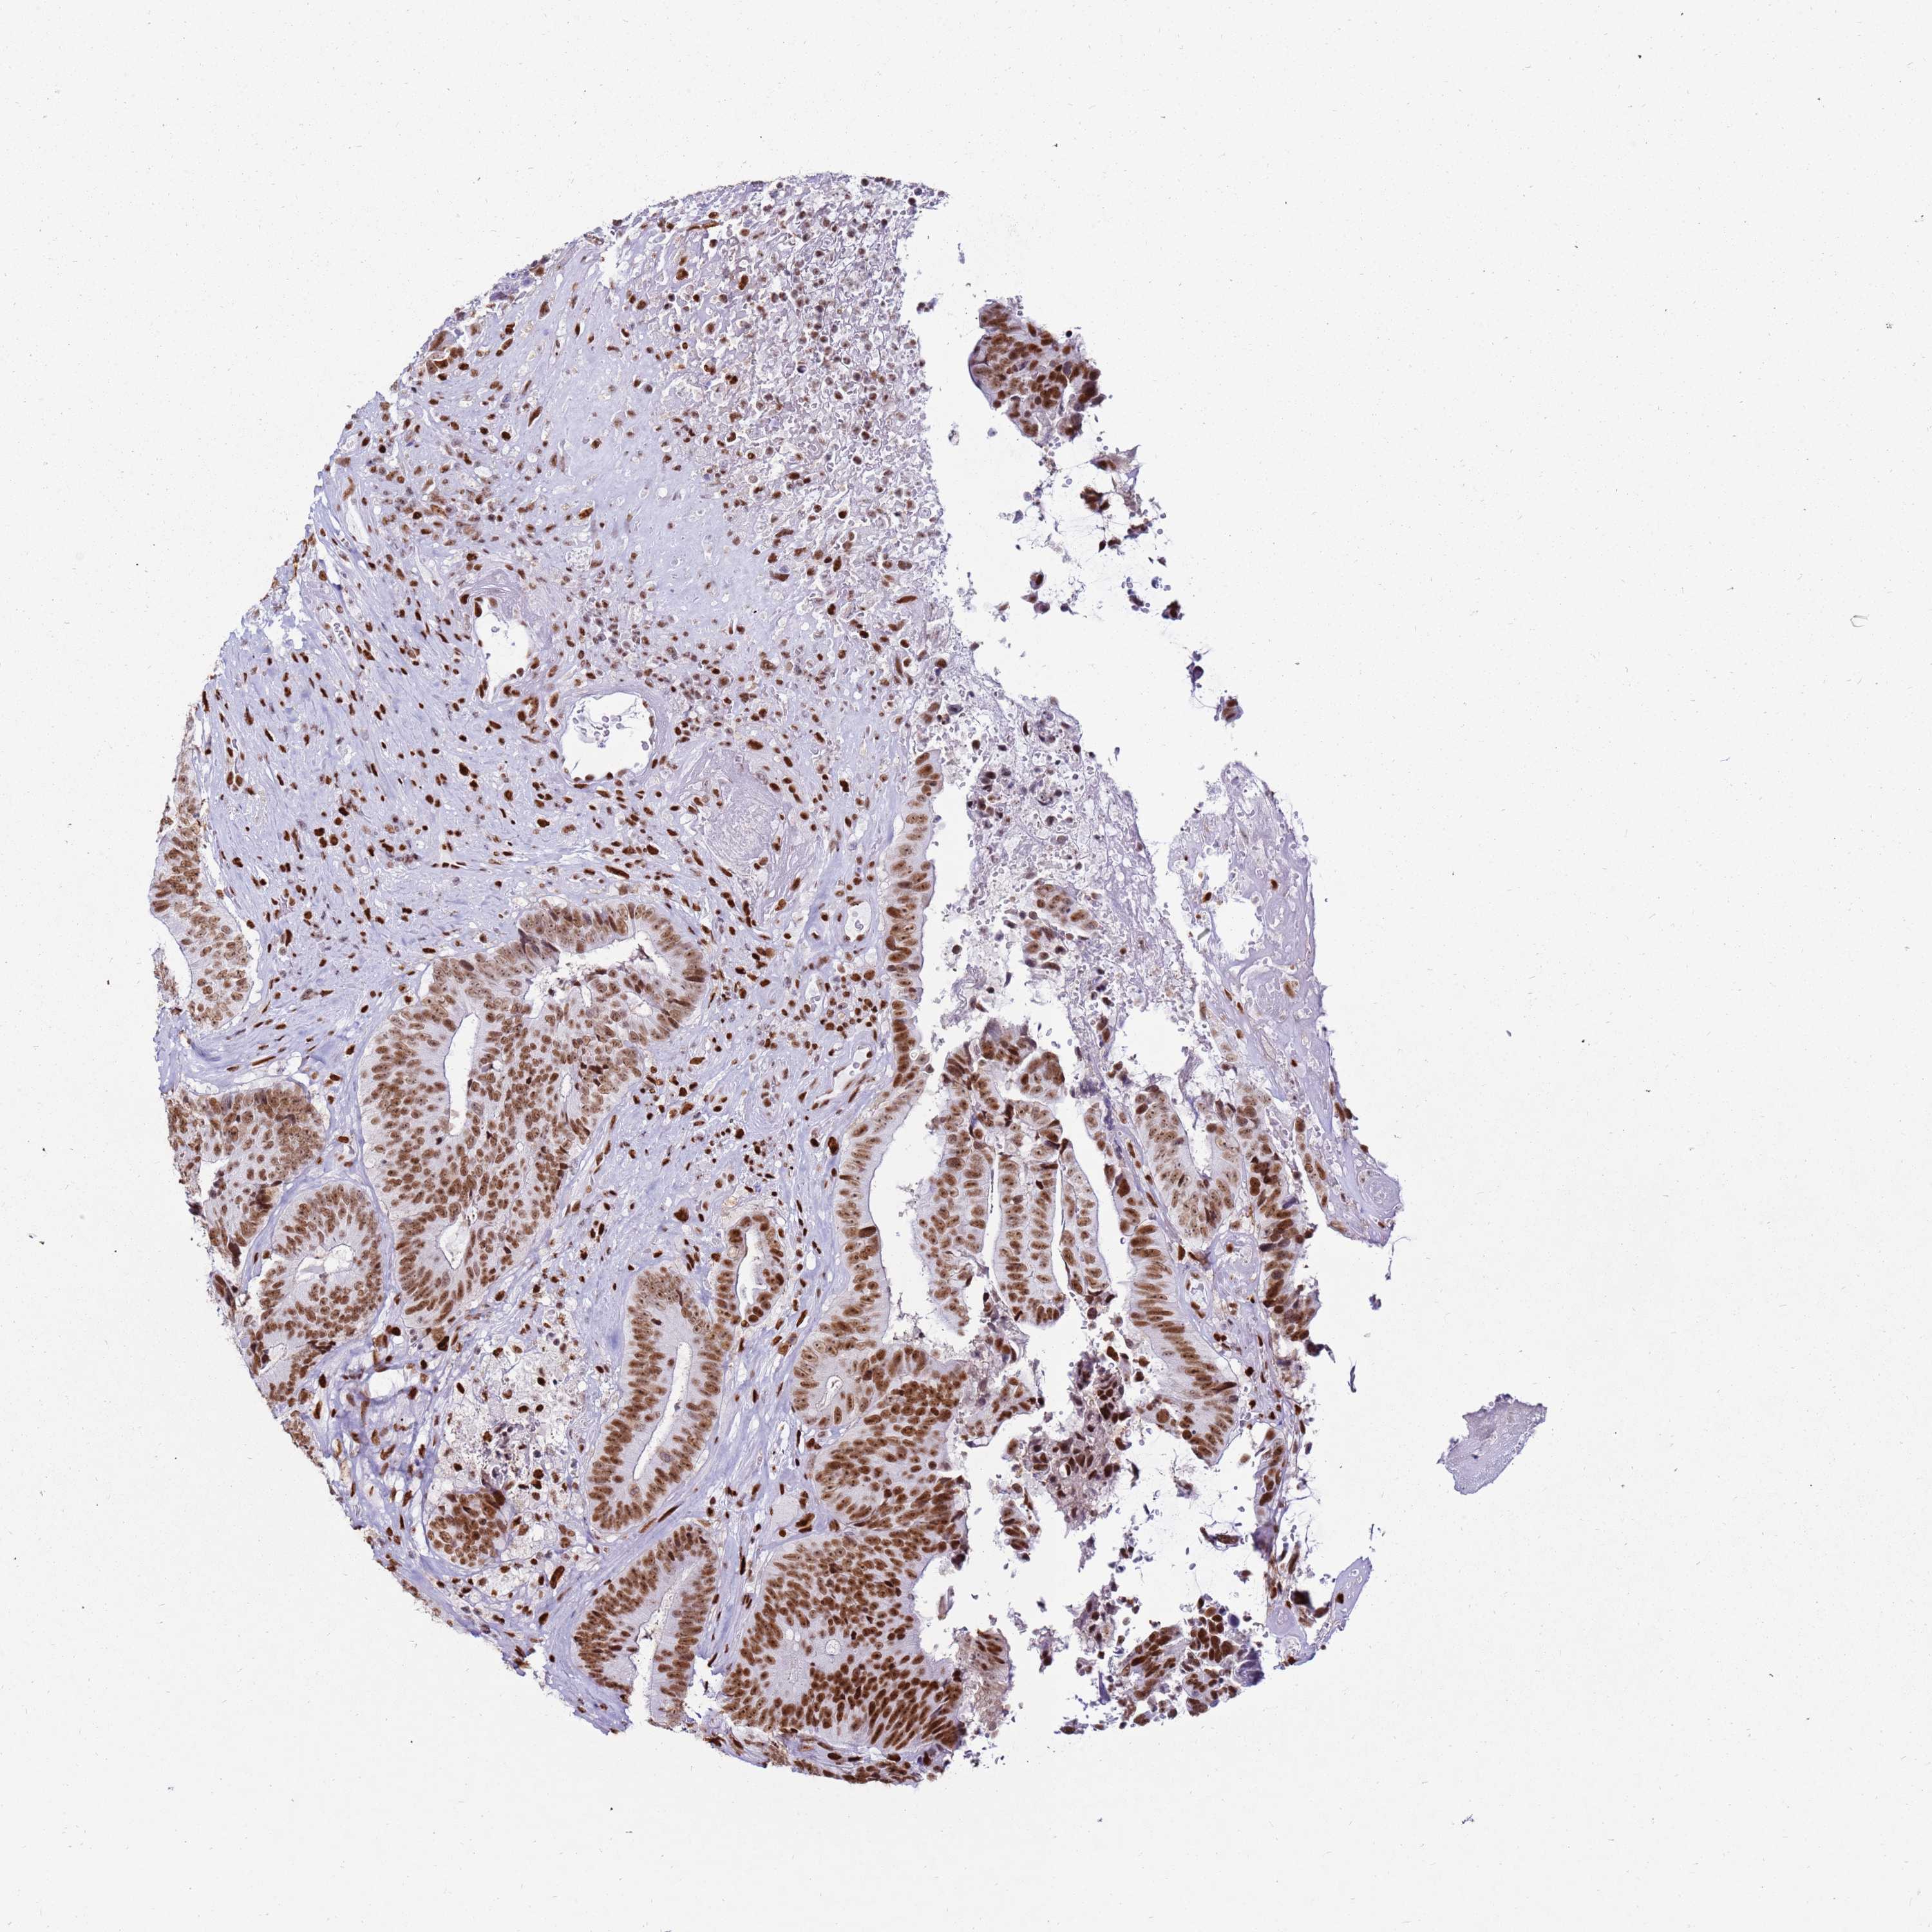

CANCER COLORECTAL CANCER Show tissue menu

Colorectal cancer

Human cancer

Colon adenocarcinoma